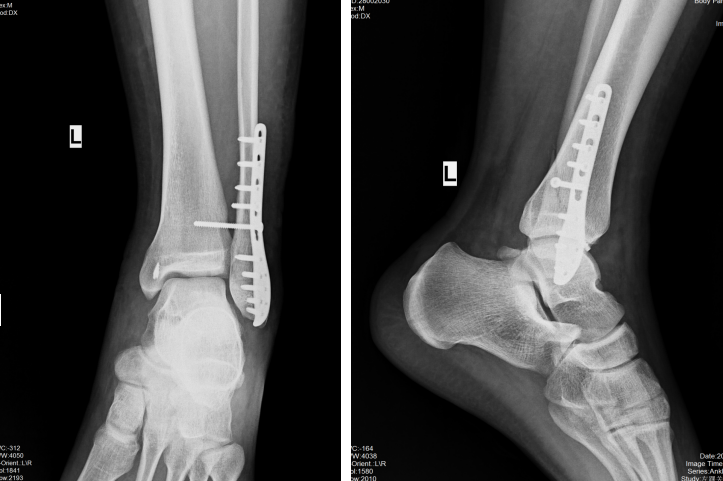

上图为踝关节骨折伴下胫腓联合损伤患者,图1、图2为下胫腓螺钉固定;图3、图4为下胫腓带袢钢板固定。(来自临床病例)